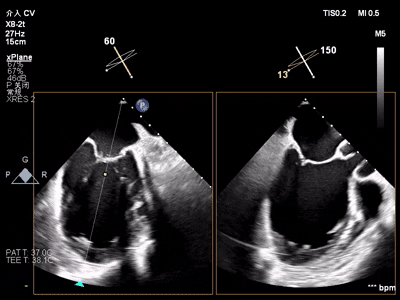

【术中操作(含关键步骤超声)】

鉴于患者术前心功能差、多支架植入的特殊情况,手术全程需兼顾“精准操作”与“保护心功能”双重要求:在全麻与经食道超声的协同引导下,团队先突破心功能受损导致的术野稳定性难题,稳步经心尖建立手术轨道与输送鞘;随后聚焦二尖瓣2偏3区精准置入一枚Ⅱf型夹合器,成功攻占这一解剖位置深、毗邻结构敏感、容错率极低而操作难度陡增的区域。

手术中,主刀术者常青教授稳定发挥,经过严谨的策略思索,挑战超精细微调整与瞬间捕获夹合,逐步逆转反流症状。从显著改善到最终完全消除,全程仅约25min的导管操作时长。在高危病例的严苛挑战下,凸显了团队操作的娴熟度与安全性。

术前术后反流对比